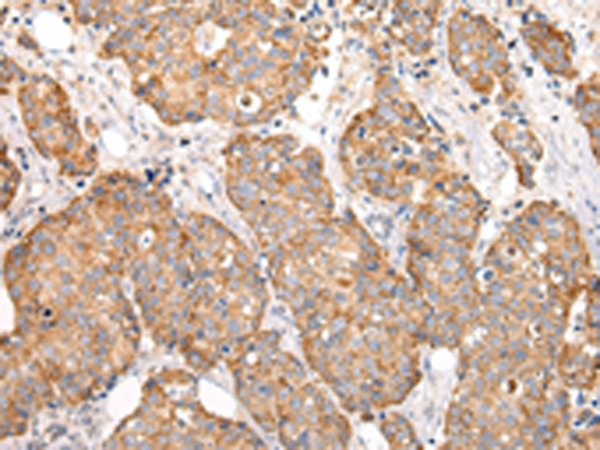

分类: 科研抗体货号: P12470别名: MRP; ABCC; GS-X; MRP1; ABC29应用: WB,IHC反应种属: Human